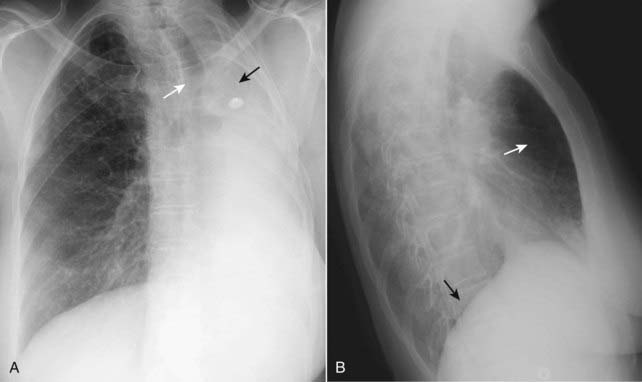

Figure 5-1 Right middle lobe atelectasis.

Frontal (A) and lateral (B) views of the chest show an area of increased density (solid white arrow), which is silhouetting the normal right heart border (solid black arrow) indicating its anterior location in the right middle lobe. On the lateral view (B), the minor fissure is displaced downward (dotted white arrow) and the major fissure is displaced slightly upward (dotted black arrow). Note the anterior location of the middle lobe.

image Right middle lobe atelectasis (see Fig. 5-1)

On the frontal radiograph:

There is a triangular density with its base silhouetting the right heart border and its apex pointing toward the lateral chest wall.

The minor fissure is displaced downward.

On the lateral radiograph:

There is a triangular density with its base directed anteriorly and its apex at the hilum.

The minor fissure may be displaced inferiorly and the major fissure superiorly.